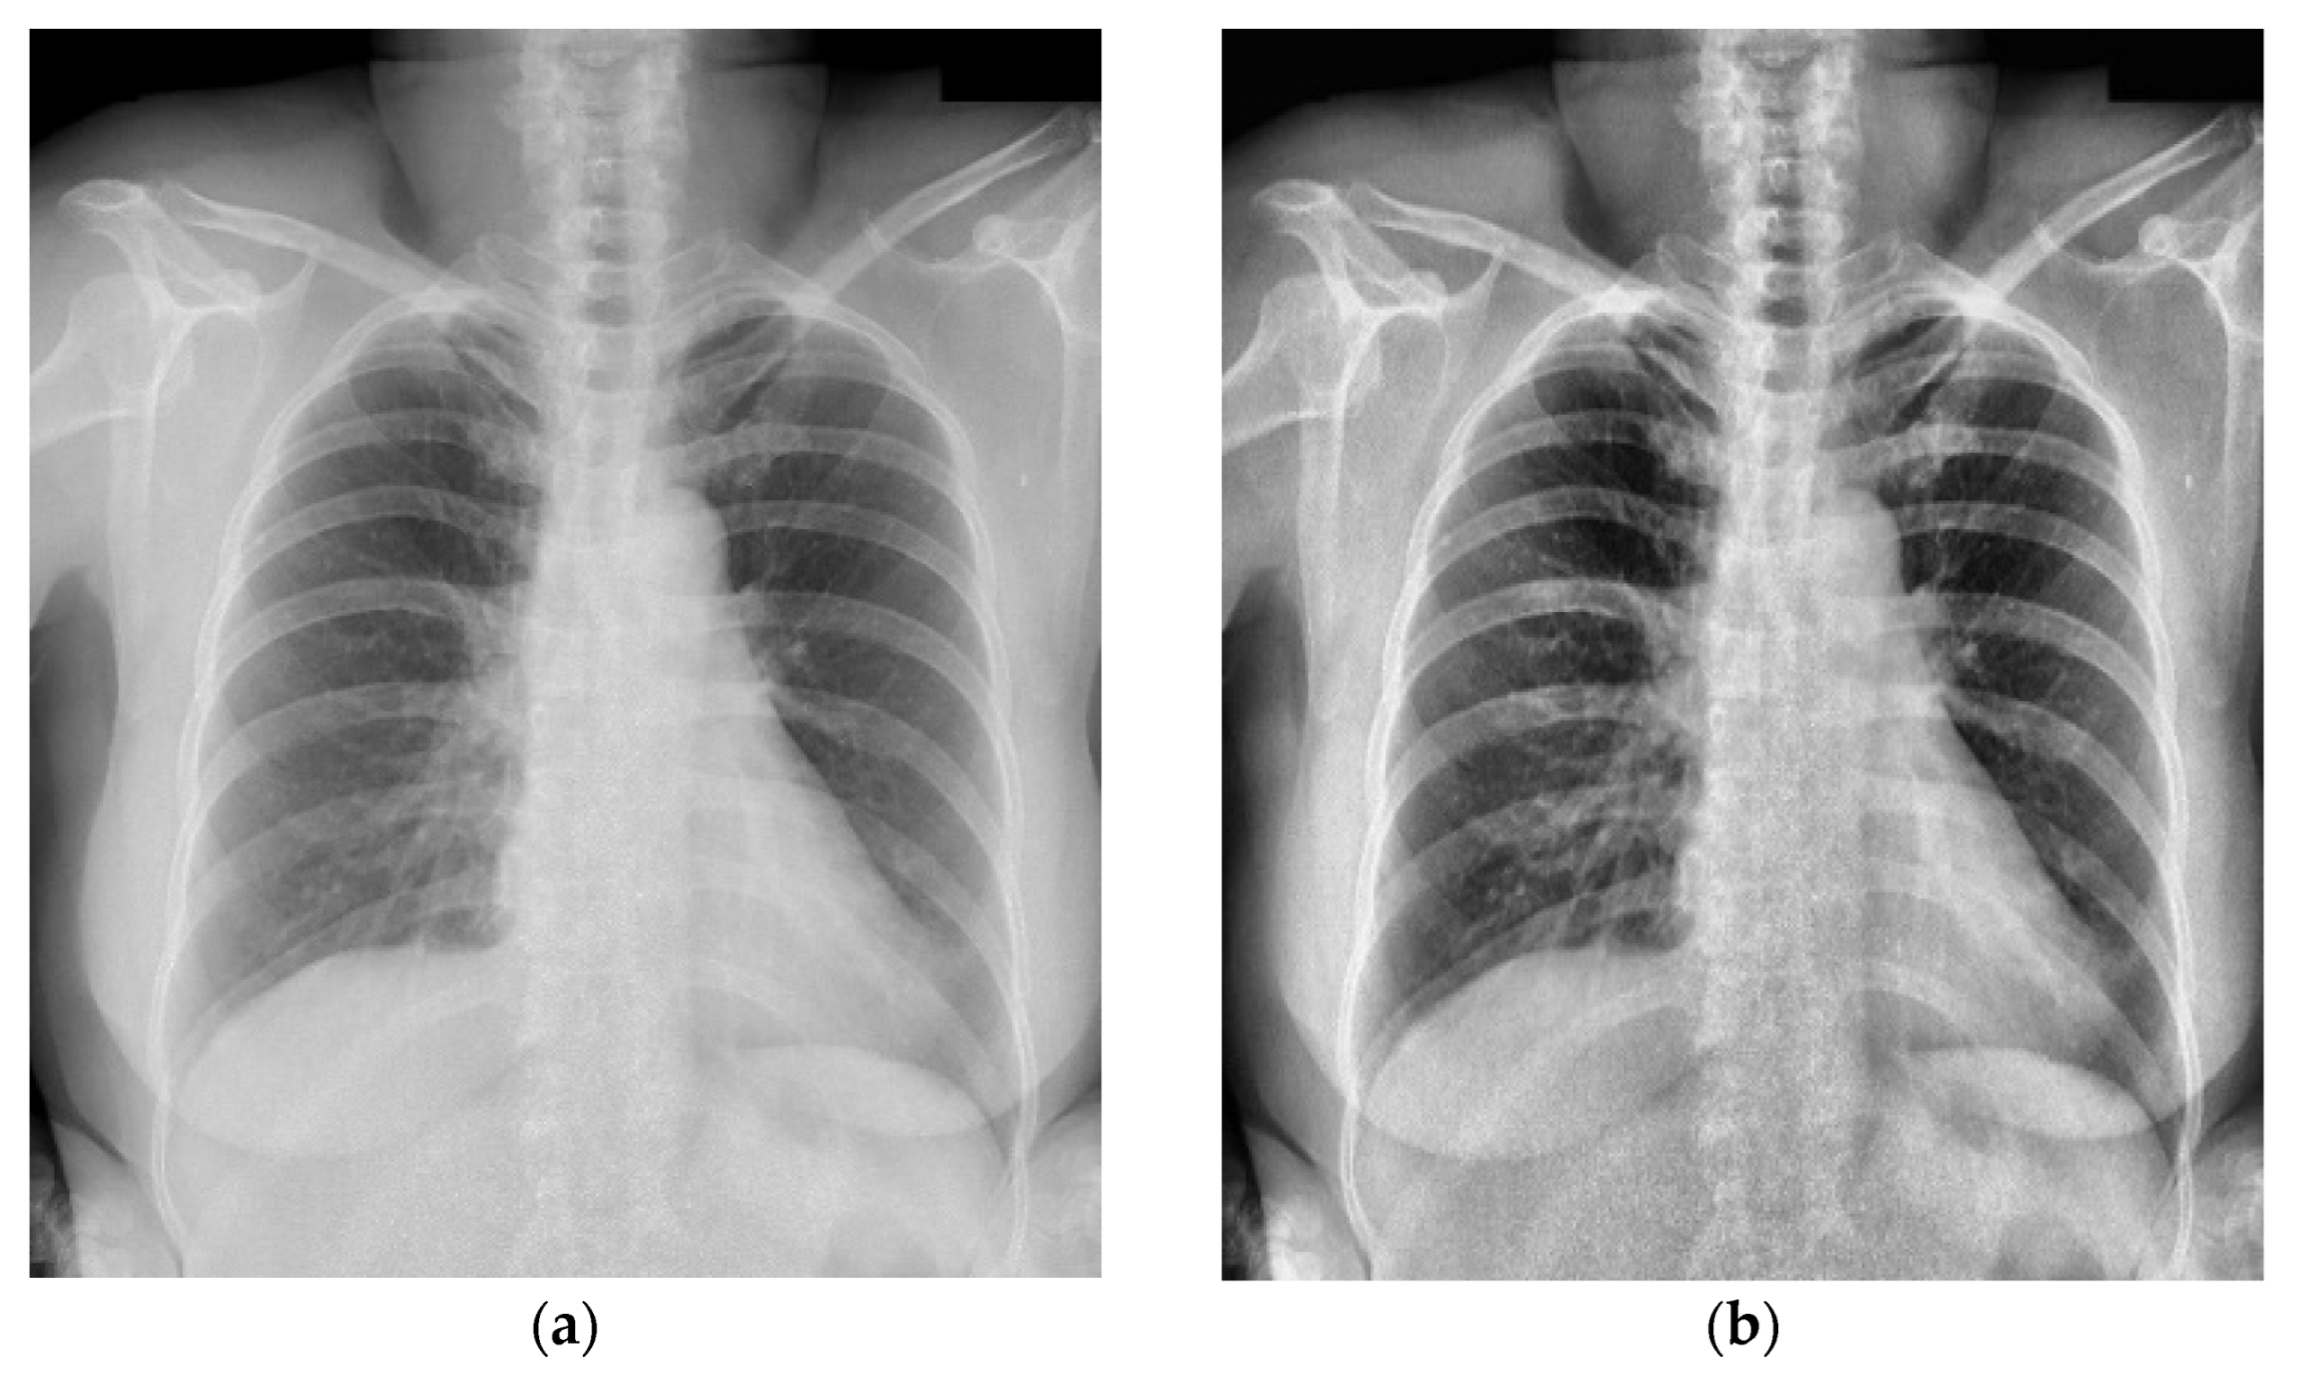

Because the chest X-ray abnormalities were independently labeled by three professional radiologists, many overlaps in annotation boxes were found in the VinDr-CXR dataset. Therefore, the weighted box fusion (WBF) technology [42] was used to reduce the overlap and redundancy of the annotation boxes. In Figure 5, the left image shows the original label and the right image shows the result obtained using WBF. It can be observed that the annotation box was significantly smaller and more concise after pre-processing. In addition, the original chest X-rays had a low contrast and brightness, which may have influenced the learning effect. For this reason, we performed image pre-processing for each sample through histogram equalization, and the results are shown in Figure 6.

Figure 6.

The image pre-processing with histogram equalization: (a) original image in the VinDr-CXR dataset; (b) pre-processing result using histogram equalization.